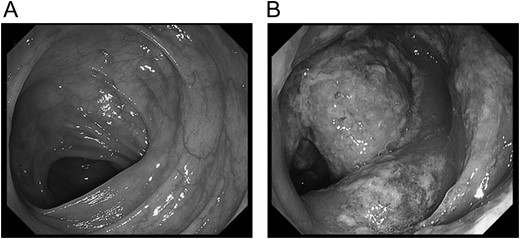

A 70-year-old man visited to our hospital with persistent difficulty in swallowing. He was diagnosed with stage II esophageal cancer by endoscopy, computed tomography (CT) and fluorodeoxyglucose-enhanced positron emission tomography. Because his oral intake was insufficient due to the obstruction of the tumor, he underwent a laparoscopic jejunostomy prior to NAC [3]. At Day 10 after the initiation of the first course of NAC with CF, he experienced slight nausea and abdominal distention, which were treated with antiemetics. At Day 14 after the initiation of NAC, he had severe abdominal pain with lower abdominal tenderness. His body temperature was 37.7 °C and heart rate was 119 beats/min. Blood tests revealed an elevation in the C-reactive protein level (3.7 mg/dL) and renal dysfunction. CT scan revealed the presence of gas within the wall of the entire colon and a small amount of free air in the mesentery (Fig. 1A). Thus, he was diagnosed with PI. A colonoscopy revealed an edema of the mucosa with a white coat, which was not observed before NAC (Fig. 2). Because there were no signs of intestinal ischemia and peritoneal irritation, we treated him conservatively; treatments included cessation of enteral nutrition, administration of meropenem hydrate and selective decontamination of the digestive tract, and oxygenation. The day after the initiation of these therapies, his abdominal pain improved. CT at Day 7 after the PI diagnosis showed that the gas within the wall had disappeared (Fig. 1B). Because NAC with CF was highly suspected to have caused PI, we abandoned the second course of CF therapy. The therapeutic effect of NAC resulted in a stable disease. We carried out video-assisted thoracoscopic esophagectomy on Day 14 after the initiation of NAC. An intraoperative laparoscopy showed no significant findings in the serosa of the colon and no intra-abdominal abnormal adhesions. He was discharged from our hospital without any complications, including PI recurrence.

Colonoscopy at the onset of abdominal pain. In colonoscopy on the day of onset of pneumatosis intestinalis, the edema of the mucous membrane and white coat were observed.